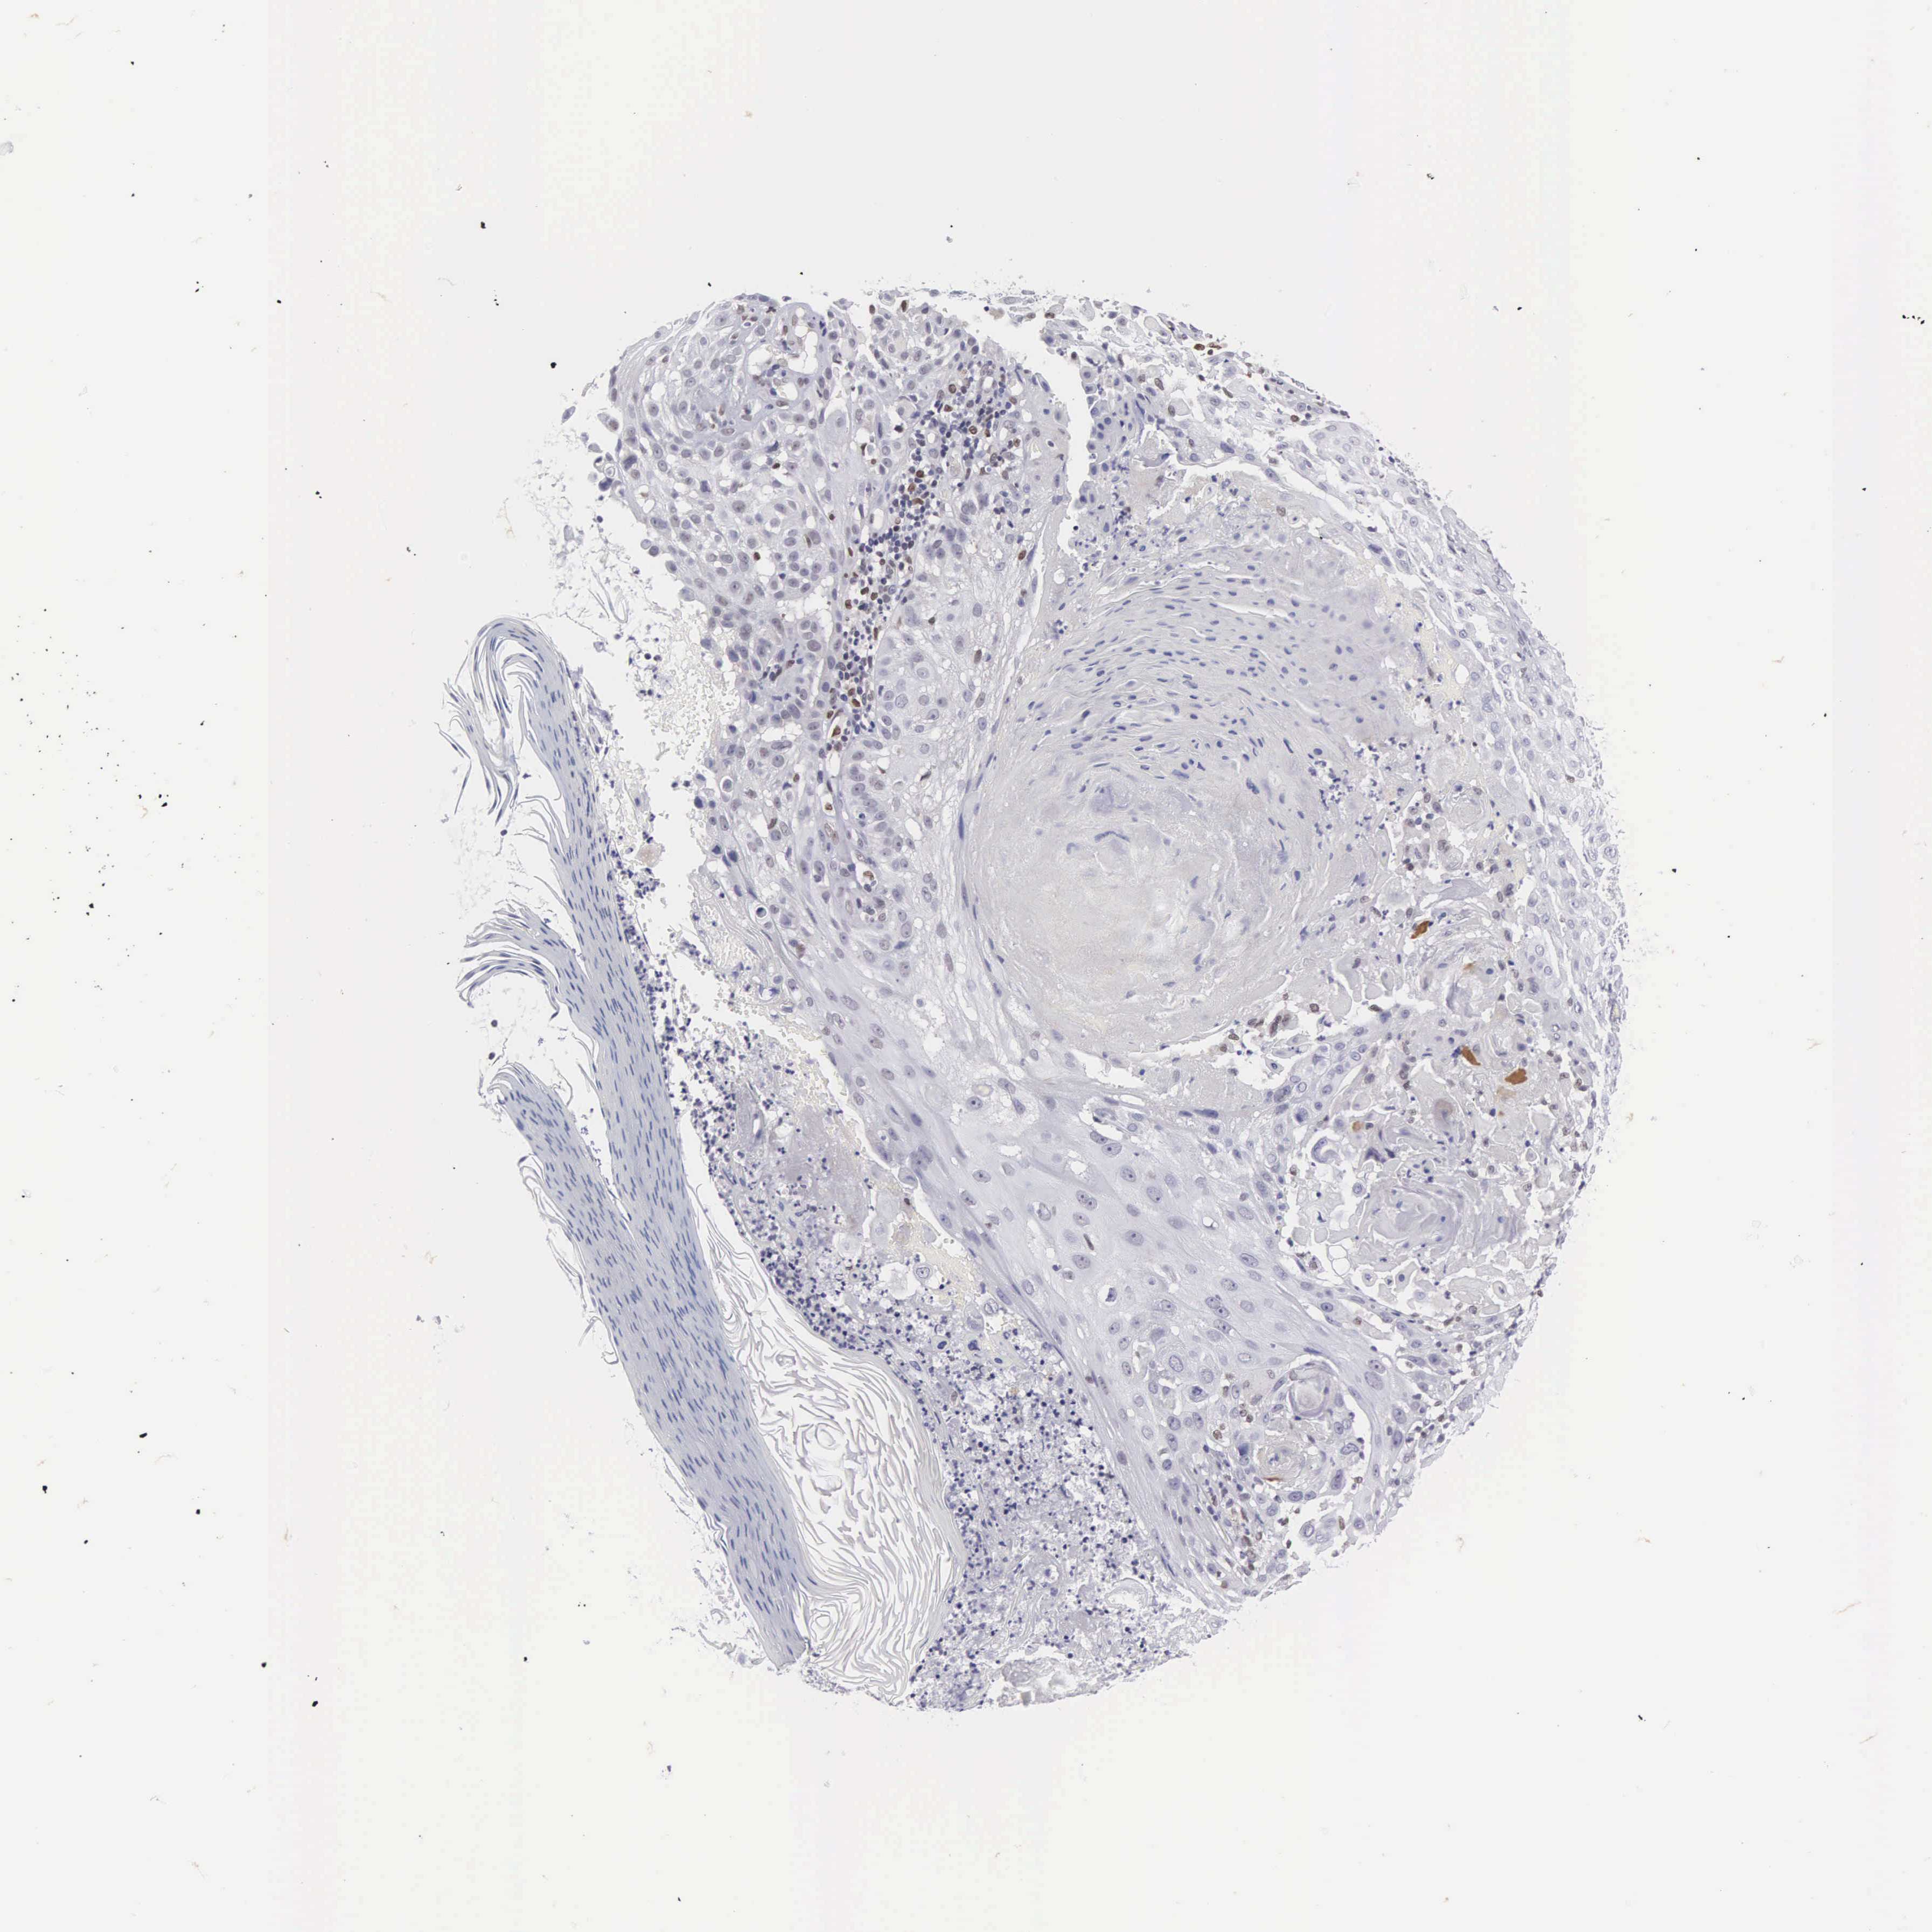

Basal cell and squamous cell cancer

SKIN CANCER - Protein expressioni

A mouse-over function shows sample information and annotation data. Click on an image to view it in a full screen mode. Samples can be filtered based on level of antibody staining by selecting one or several of the following categories: high, medium, low and not detected. The assay and annotation is described here.

Each image is clickable and will lead to virtual microscopy that enables deeper exploration of all samples and also displays staining intensity scores, fraction scores and subcellular localization as well as patient and tissue information for each sample.

Antibody HPA000264

Staining

High

Intensity

Strong

Quantity

>75%

Location

Nuclear

Squamous cell carcinoma, NOS

Basal cell carcinoma